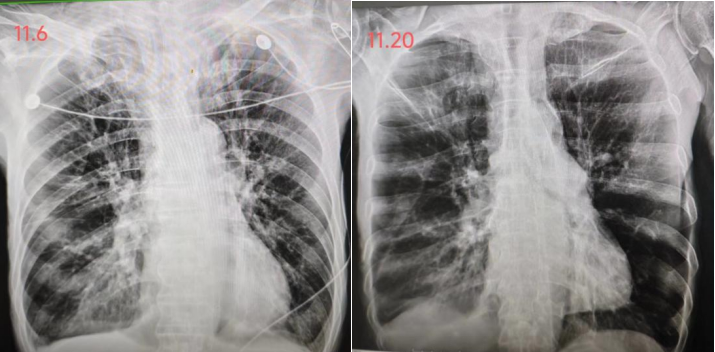

11月20日胸部X线片可见两肺散在炎症,两肺慢支-肺气肿改变,较前吸收图5

图片

5  患者胸部X线片变化